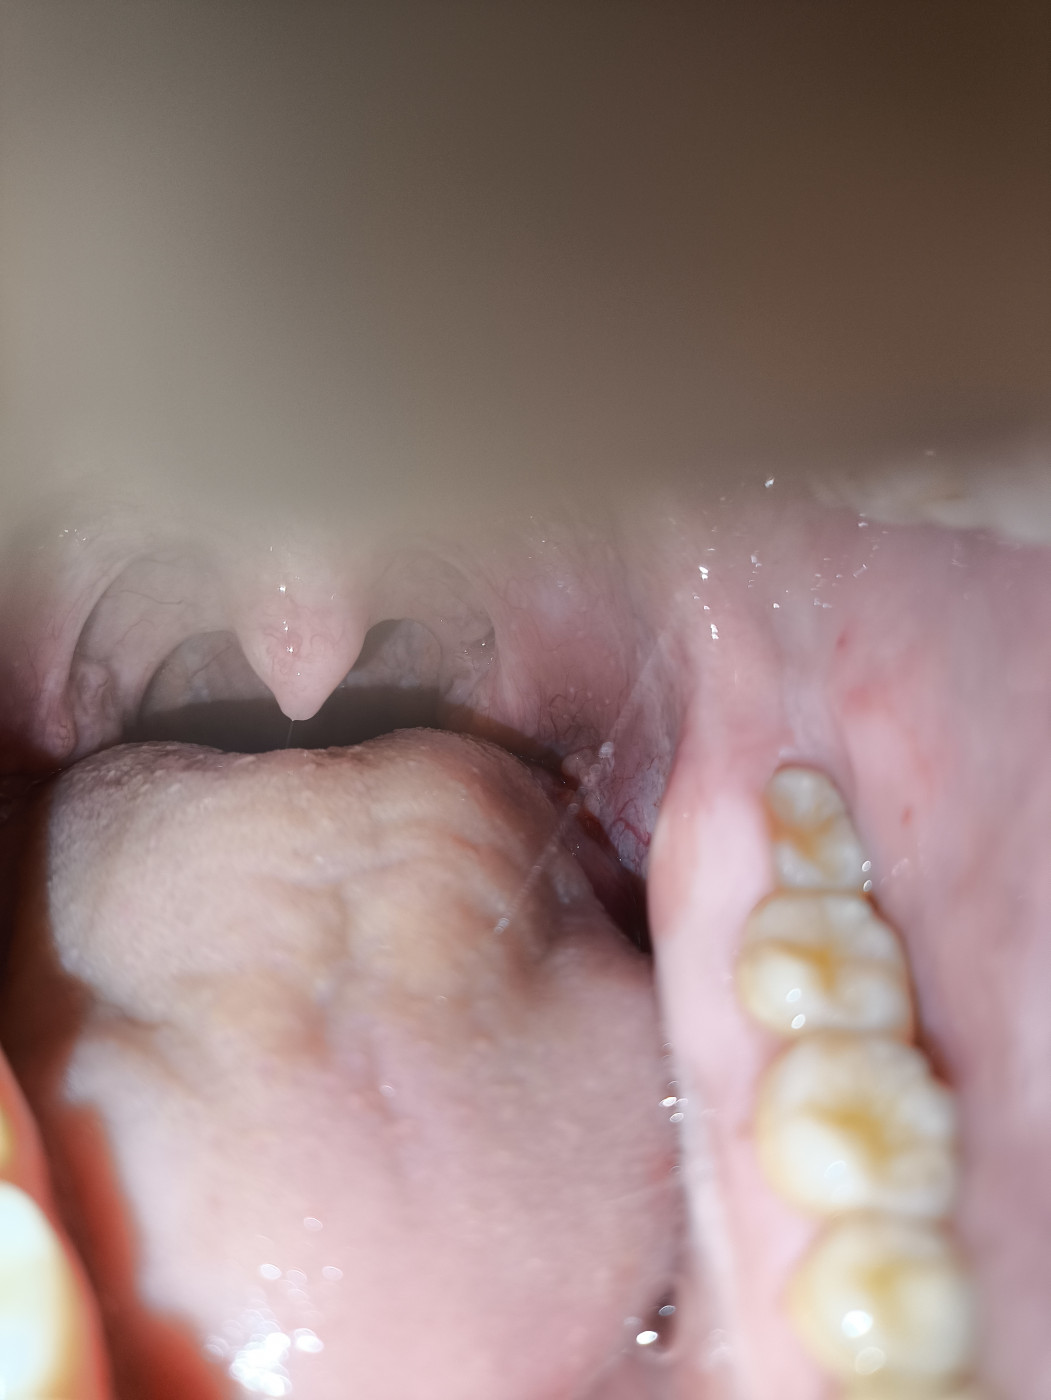

Воспаление миндалин, белые волдыри.

Белый налет на миндалинах во время беременности